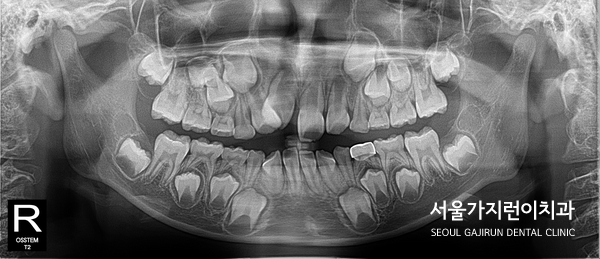

먼저 해당 사례의 경우 7세의 어린이였는데요. 혼합치열기에 있는 어린이 환자였기 때문에 한번에 교정을 완료할 수는 없지만 당장 잘못된 방향으로 맹출되고 있는 치아 교정은 할 필요가 있었습니다. 사진을 보면 상악 우측 중절치와 측절치의 맹출방향이 이상한 것을 눈으로도 확인이 가능했는데요. 상악 전치 배열 및 기울기, 높이를 졍상적인 범위로 조절하기 위해 튜브교정으로 진행을 했습니다. 이 경우는 필요하다면 영구치가 맹출될 때 2차 교정을 진행하기로 결정할 수도 있는데요. 앞니만 교정하면 되는 상황이었기 때문에 단기 부분교정에 맞는 튜브교정으로 적용을 해봤습니다.

참고로 7살 어린이의 전후 사진을 비교해보면 교정을 시작한지 약 5개월만에 정상적으로 자리를 잡은 것을 확인할 수 있는데요. 앞니에 한정된 교정이었기 때문에 단기간에도 치료를 해볼 수 있습니다. 치아의 배열이 달라진 것을 파노라마 사진으로 확인이 가능한데요. 겉으로 보이지 않지만 혼합치열기의 환자분들은 숨은 치아들이 있기 때문에 초반에 맹출하는 치아들을 제대로 관리하지 못하면 영구치에도 영향을 미쳐 적절한 시기에 교정을 시작하는 게 좋습니다. 7살 교정? 너무 이른 거 아닌가요?에 대한 답변이 되셨을까요.